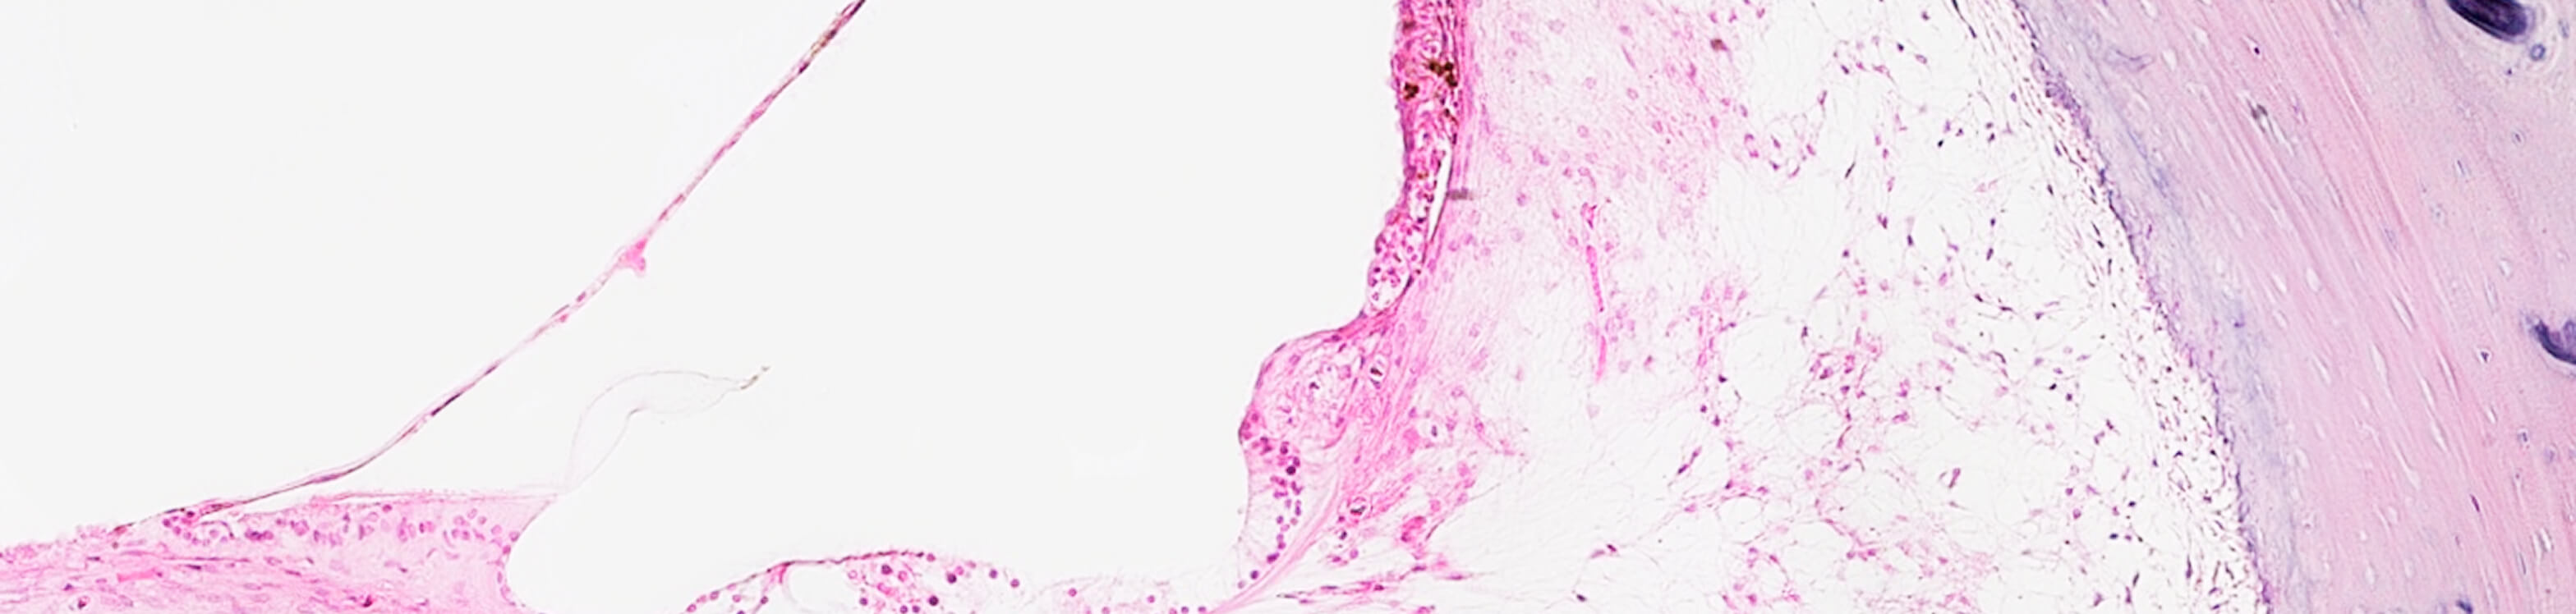

Immunohistochemical Protocols

The NIDCD National Temporal Bone Laboratory at UCLA standardized immunohistochemical protocols and methods to study the normal and pathological human inner ear. Given the scarcity of tissue available and the high cost of processing the human temporal bones using the traditional methods we proposed alternative choices such as microdissection, frozen and paraffin sectioning. To optimize the use of invaluable celloidin embedded sections of the human temporal bone our laboratory and others, have been developing methods to remove celloidin from the tissue sections and subsequent antigen retrieval. The best process and preserved tissue methods are being shared with inner ear basic researchers to corroborate their previous findings in animal models. We describe immunofluorescence protocols for allow the identification of several antigens in the same sections.